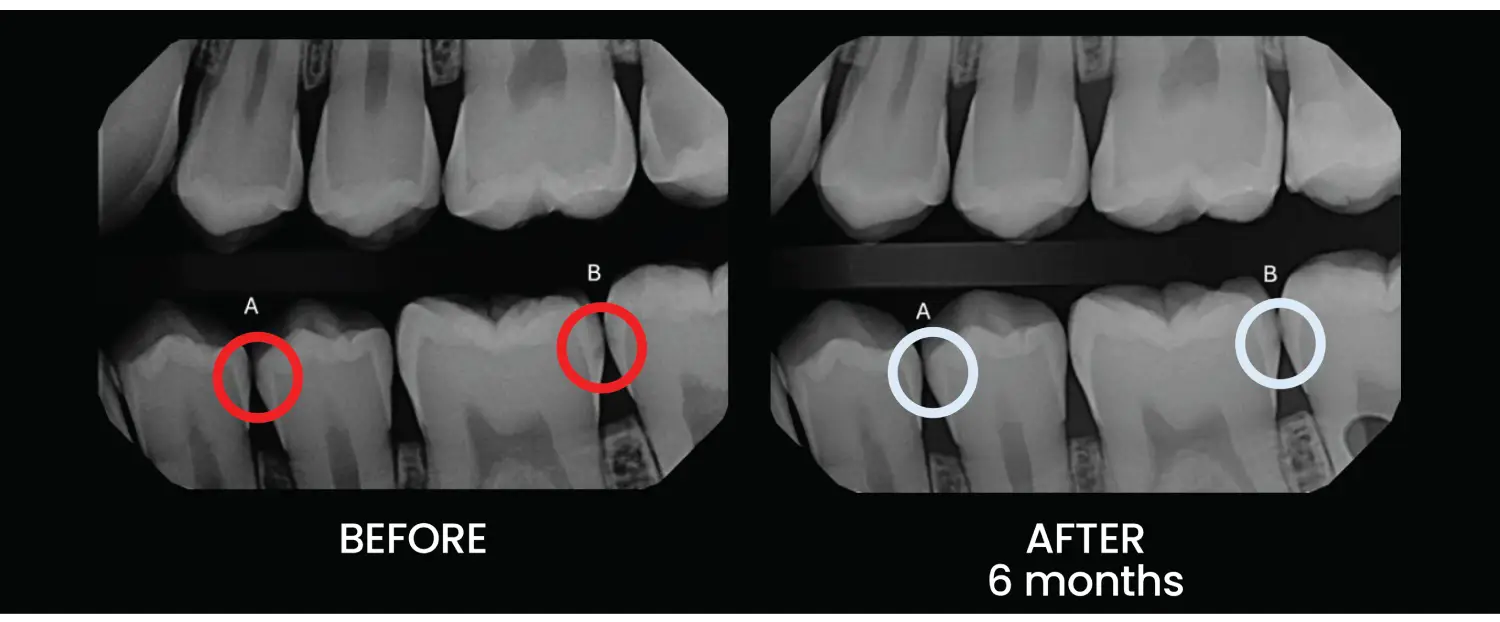

We apply a state-of-the-art remineralization formula that contains the same essential minerals found in your natural enamel. This helps repair weakened areas at the microscopic level.

The formula penetrates deeply into the enamel to stop early decay, strengthen surrounding tooth structure, and preserve your natural tooth—no drilling required.